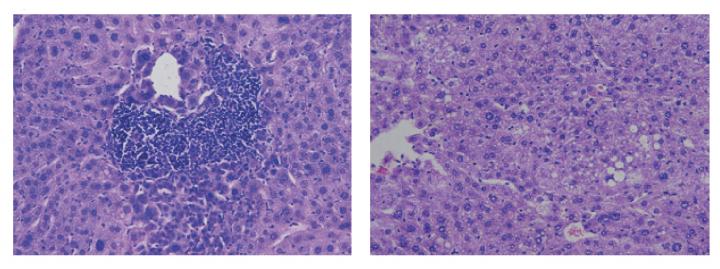

Similar to humans, male mice are more prone to HCC than females. Sabio and colleagues found that increased levels of adiponectin in female mice protect them from HCC. The researchers determined that the hormone activates two proteins inside liver cells, known as p38? and AMPK, that block cell proliferation and impair tumor growth.

Inhibiting testosterone production in male rodents increased their adiponectin levels and reduced tumor growth. Sabio and colleagues found that testosterone activates a protein in fat cells called JNK1 that inhibits adiponectin production.